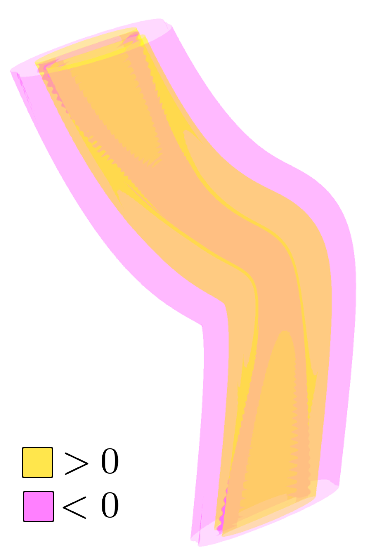

, , and modulate the respective components of the canonical Laplacian of Gaussian () filter oriented along the principal directions of . It is clear that given any arbitrary orientation as an orthonormal basis similar to , the proposed dictionary of filtering kernels can steer by computing the rotation transform, which maps the integral orientation basis of each Gaussian kernel on . Together with the SLoGS filtering kernel , we determine the second-moment matrix associated to the filter impulse response by adopting the ellipsoid model in the continuous neighborhood of . A symmetric tensor is derived from the eigendecomposition of as , where is the diagonal matrix representing the canonical unitary volume ellipsoid

the respective semiaxes’ lengths. Conversely from , which is indeterminate, the tensor field is a symmetric positive definite (SPD) matrix for any . Here, the definition of the tensor kernel in (4) can be further reformulated exploiting the intrinsic log-concavity of . By mapping , a convex quadratic form is obtained, so that is an SPD, as the modelled tensor . In either case, the manifold of tensors can be mapped into a set of 6 independent components in the Log-Euclidean space, which greatly simplifies the computation of Riemannian metrics and statistics. We refer to [3] for a detailed methodological description. The continuous and smooth tensor field inherits the steerable property. Similarly to diffusion tensor MRI, the kernel shows a preferred diffusion direction for a given energy potential, e.g. the scalar function itself (fig. 1). This allows to define an arbitrary dictionary of filtering kernels (DFK) that embeds anisotropy and high-order directional features to scalar curvilinear templates, which enhances and locally resembles typical, smooth vessel patterns. Together with the arbitrary SLoGS DFK, we also introduce an extra pair of non-curvilinear kernels for completeness. These are the pseudo-impulsive , an isotropic derivative filter given by the Laplacian of Gaussian of , representing a Dirac delta function for . Also, the uniformly flat is another isotropic degenerate case, where the Laplacian of Gaussian derives from , which is assumed to be a uniform, constant-value kernel for . The purpose of introducing the extra kernels is to better contrast regions that most likely relate to vessel boundaries and to image background, respectively. Although and have singularities, ideally they represent isotropic degenerate kernels. Therefore we associate pure isotropic tensors for any given , so that (Identity). The respective directional kernel bases are undetermined.

where is the integral normalizing weight-map accounting for all vessel, boundary and background components; is the modulating SLoGS filter response at as in (7); is the steered Gaussian impulse response associated to the kernel ; is the Hann smoothing window in the neighbourhood centred at , and is one of the 6 components of the discrete steered tensors patch in the Log-Euclidean space. Note that all 6 tensorial components are equally processed, and that the neighbourhood and the SLoGS tensors patch have the same size. In (8), integrates also the isotropic contributions from vessel boundaries and background to better contrast the tubular structures’ anisotropy and to reduce synthetic artifacts surrounding the vessels (fig. 1). In particular, is averaged with an identically null tensor patch in the Log-Euclidean space in correspondence of boundaries and background, and is computed as in (7), where the image negative of is considered. Lastly, the connected vesselness maps and the associated synthetic tensor field are reconstructed by adding adjacent overlapping blocks in the OLA 3D grid for the given scale .

The respective tensor fields (TF) synthesized on both HCP and PC show consistent features. The TF’s characteristics are in line with the connectedness of CVM: enhanced and connected vessels are associated with high anisotropy, whereas background areas show a predominant isotropic component.